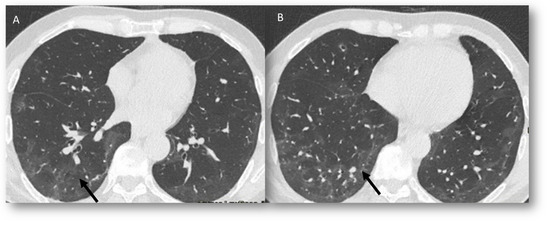

| RRP | Target area | Ground-glass opacities and consolidative opacities. | Unknown (A non-immune fixed drug reaction-like condition, dysregulated release of reactive oxygen species, abnormalities of tissue vasculature and impaired DNA repair). |

| RP | Target area | Ground-glass opacities and consolidative opacities. | Direct damage to the DNA and indirect damage through the production of reactive oxygen species (ROS), causing changes in vascularity and capillary permeability, activation of the inflammatory response and alteration of immunological response |